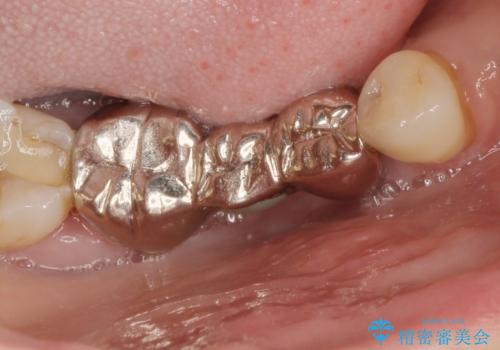

- 「銀歯だらけの歯を変えたい。他院で歯周病と指摘されたがクリーニング以外何もしてくれない。」、とセラミック治療歯周病治療を希望され来院されました。

検査の結果、感染根管や欠損、歯周病により残すことのできない歯、等多々問題が認められます。

残すことのできる歯できない歯を選別し、欠損部にはインプラントによる咬合機能の回復、保存できる歯には歯周病治療・根管治療を行う治療計画としました。